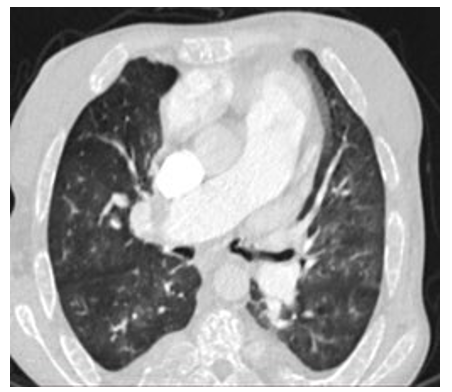

A patient 28-year-old male who was receiving periodic trans- fusions with intermittent chelation therapy for Sickle Cell Dis- ease (SCD) came to our clinic with complaint of dyspnoea on exertion (DOE) in the past two years. The patient was followed up at the haematology department. On the physical examination the patient had distended jugular veins, high abundance ascites and hepatomegaly. At the electrocardiogram revealed a regular rhythm and a completely right bundle brunch block. At echo- cardiography, LVEF was about 60%. The right ventricle is very dilated in Figure 2 with massive tricuspid insufficiency due to a diastasis in tricuspid valve.

Figure 2: Cardiac CT Scan: Very Dilated Right Ventricle in a SCD Patient

A lower right ventricular function: free wall TDI peak systol- ic velocity was 4 cm/sec. Estimation of systolic pulmonary ar- tery pressure from tricuspid insufficiency was about 120 mmHg which was very high and supra-systemic. The patient was ex- plored by cardiac CT-scan revealing advanced pulmonary hemo- chromatosis in Figure 3, no pulmonary emboli and very enlarged right cardiac cavities. Our patient died of acute chest syndrome during hospitalization [1].

Figure 3: Pulmonary CT scan, Pulmonary Hemochromatosis in a SCD Patient